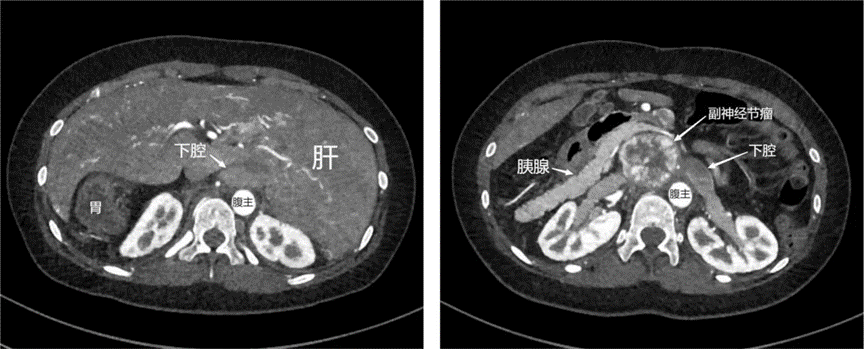

全腹增强CT (2023-6-13,苏州大学附属第一医院,2151315):后腹膜上位53 mm*38 mm,考虑异位嗜铬细胞瘤;肝、胰腺、胃及下腔静脉反位。

全主动脉CT增强造影(2023-10-17,上海长海医院,ZH231017CT08035):心血管术后改变,右侧肺动静脉瘘可能,升主动脉瘤;右肺及左上肺渗出,淤血可能;腹膜后结节,副神经节瘤可能大;胃腔、胰腺大部分位于右上腹(镜像反位);甲状腺右叶结节。

影像分析

图1 二维增强CT影像

图2 三维立体成像

手术难点1

肝、胰腺、胃、十二指肠及下腔静脉反位。胰腺后方肿瘤通常采用kocher切口,将胰头及十二指肠翻向左侧,可充分暴露肿瘤及下腔静脉,但此患者腹腔脏器转位,且解剖结构并不是简单的镜像,如十二指肠降段不是在胰头左侧,而是在胰头后方,不但无法采用传统kocher切口,亦无法采用“反kocher切口”,术中操作具有反直觉、反习惯的特点,需要边手术边摸索解剖结构,易误伤胰腺、十二指肠及下腔静脉,造成胰瘘、肠瘘及大出血,危及生命,造成严重的术后并发症。

应对策略1

术前完善腹腔增强CT及三维重建,深入研究二维及三维图像,在脑中构建器官及大血管走形的解剖图像,通过这种“认知融合”制定流程化的手术方案,并预估术中可能出现的特殊情况,设计好预案,如十二指肠破裂,可能要行胰十二指肠切除。术中操作轻柔,以钝性分离为主,尽可能避免损伤胰腺、十二指肠及下腔静脉。